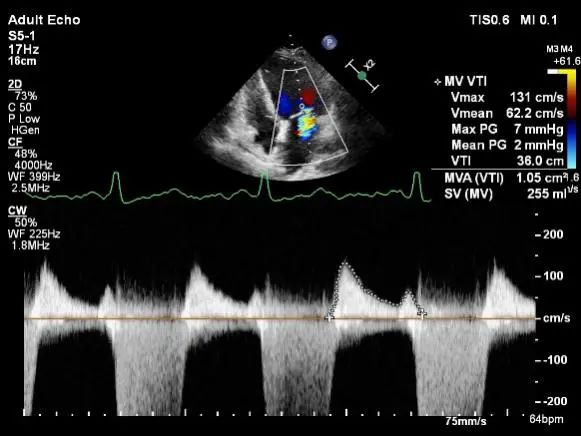

术后肺静脉频谱

二尖瓣瓣口面积及平均跨瓣压差评估(5mmHg)

患者麻醉方式同样采取全麻,建立静脉通路后,穿刺右侧股静脉后,预埋ProGlide缝合器后,送导管至房间隔部位,成功穿刺房间隔后进入左房,调整导管角度,顺利到达二尖瓣目标位置,后在X线及食道超声联合辅助下,宋光远教授使用2枚XTR二尖瓣夹,在精确定位后,准确夹合二尖瓣A2-P2以及A3-P3区域,患者收缩压即刻上升30mmHg,左心房收缩压由62mmHg下降至28mmHg,术中测反流面积明显减少,肺静脉多普勒波形由反向恢复正常。手术顺利结束,术后患者即刻苏醒,安返病房。

第二枚XTR夹子释放,返流明显减少

三维超声心动图显示第二枚XTR夹子释放